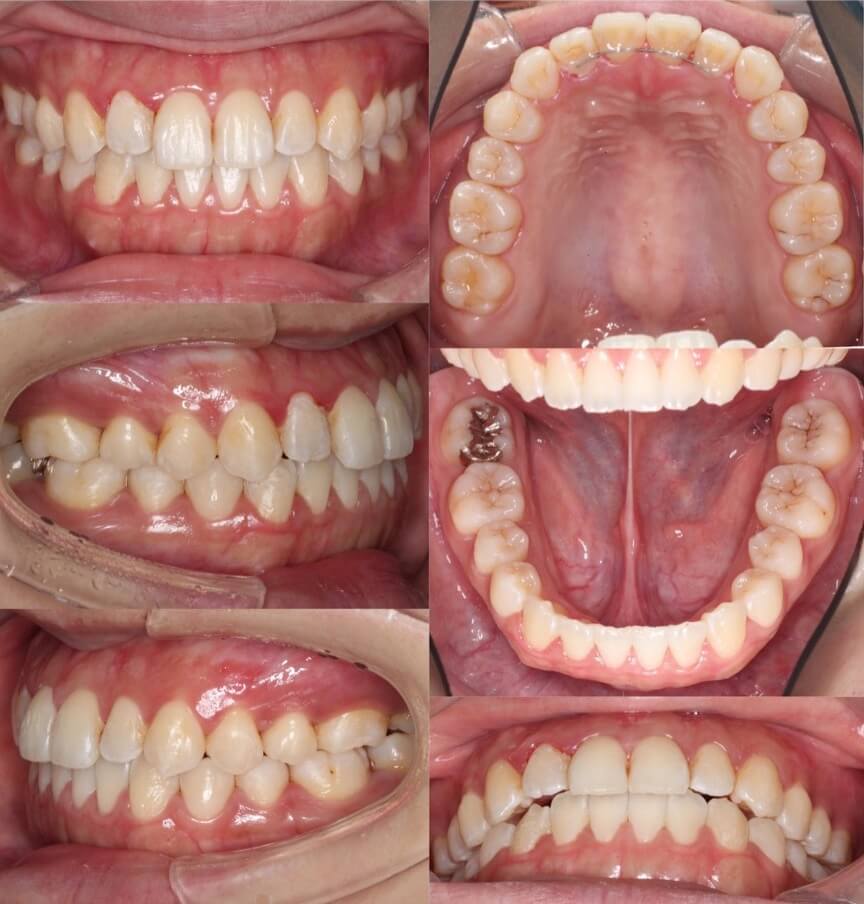

20代女性・唇側矯正装置・上下抜歯

八重歯があり上の歯並びに強いがたつきがある受け口ケースです。反対咬合で小臼歯を抜歯する際は上は5番を抜歯することが多いです。これは、上の前歯を後ろに引きすぎないようにするためです。下の歯並びには前歯の後方移動を効率化するために、2本ワイヤーを使用しています。

<症例概要> 難易度 ★★★★☆

主訴:受け口・前歯のガタガタ

年齢・性別:大学生女性

住まい:千葉県八千代市

症状:反対咬合・重度叢生

治療方針:上下小臼歯抜歯・上顎歯列拡大・空隙閉鎖

治療装置:唇側矯正装置

固定装置:上リンガルアーチ・III級顎間ゴム

抜歯:上第二小臼歯・下第一小臼歯(計4本)

治療期間:2年3か月

リテーナー:上下フィックスタイプ+プレートタイプ

治療費用:990,000(税込)

代表的副作用:痛み・治療後の後戻り・歯根吸収・歯髄壊死・歯肉退縮